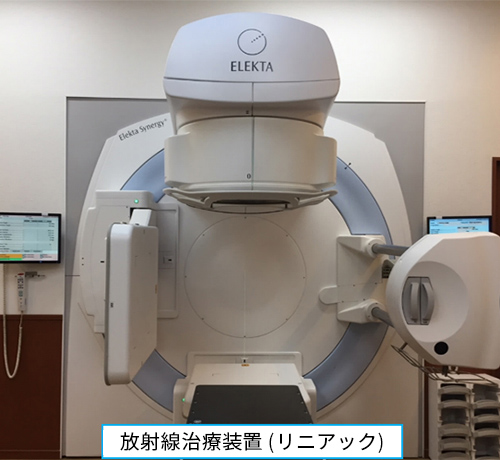

治療装置の進歩により、病巣へ高い精度で正確に照射することが可能になりました。外部照射は、使用する放射線、方法によりいくつかの種類があります。

強度変調放射線治療 (IMRT)

病巣に高い放射線量を集中させ、従来の治療法と比較して周囲の正常組織への影響を抑えることが可能な治療法です。

画像誘導放射線治療 (IGRT)

照射の直前や照射中に得られる患者さんの画像情報(X線画像等)を基に日々の放射線治療時の位置誤差を補正しながら正確に治療する技術です。